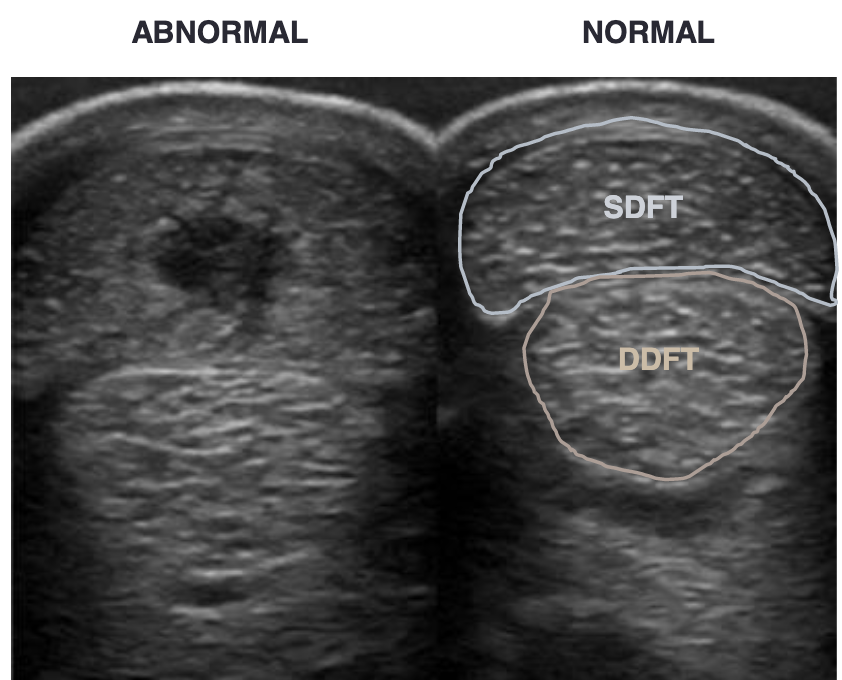

label equine distal limb ultrasound (top to bottom)

superficial digital flexor

deep digital flexor

check ligament

suspensory ligament

what is this

left= normal

right= deep digital flexor tendonitis

yellow arrows= tear in deep digitial flexor tendon